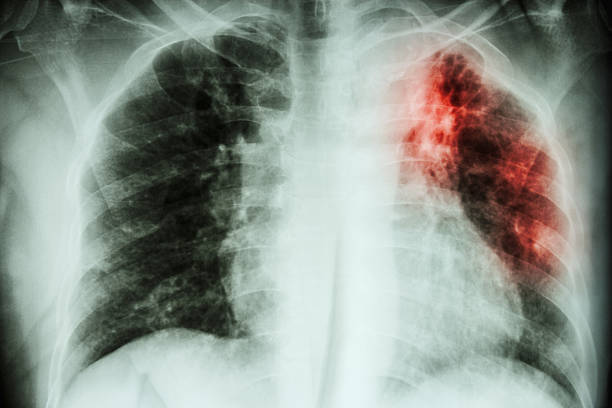

Туберкулезная инфекция относится к числу самых распространенных заболеваний по всему земному шару, которое диагностируется у людей разных возрастных групп, независимо от их пола, расовой принадлежности и социального положения в обществе. Согласно официальной статистике, сегодня в мире насчитывается более 1,6 млрд. больных туберкулезом, практически половина из которых страдает тяжелыми формами болезни и активно заражает своих окружающих. Единственной профилактической мерой, позволяющей предупредить заболевание, в настоящее время является прививка против туберкулеза. Хотя даже своевременная и полноценная вакцинация не дает уверенности, что человек не заболеет. Тогда, нужна ли прививка от туберкулеза? Зачем ее ставят и какую вакцину лучше при этом выбрать?

Туберкулезный процесс представляет собой болезненное самочувствие, которое сложно поддается лечению. Пациенты, сумевшие побороть недуг, отмечают, что противотуберкулезная терапия могла длиться у них годами, оставив после себя ряд осложнений и негативных последствий. Почему так сложно избавиться от болезни? Дело в том, что микобактерии туберкулеза обладают многоуровневой защитой, а поэтому резистентные к большинству противобактериальных препаратов, резким температурным перепадам, ультрафиолетовому излучению и тому подобное. К тому же, после проникновения в человеческий организм, они быстро снижают функцию иммунной системы, что делает невозможным процесс избавления от них. Туберкулез нуждается в массовой профилактике, так как ежегодно уносить миллионы жизней людей, не имеющих специфической защиты от инфекции.

Понятно, что прививка не способна защитить человека от проникновения в организм инфекционных агентов, но ее действия достаточно, чтобы предупредить осложненные формы недуга и приостановить распространение туберкулеза.